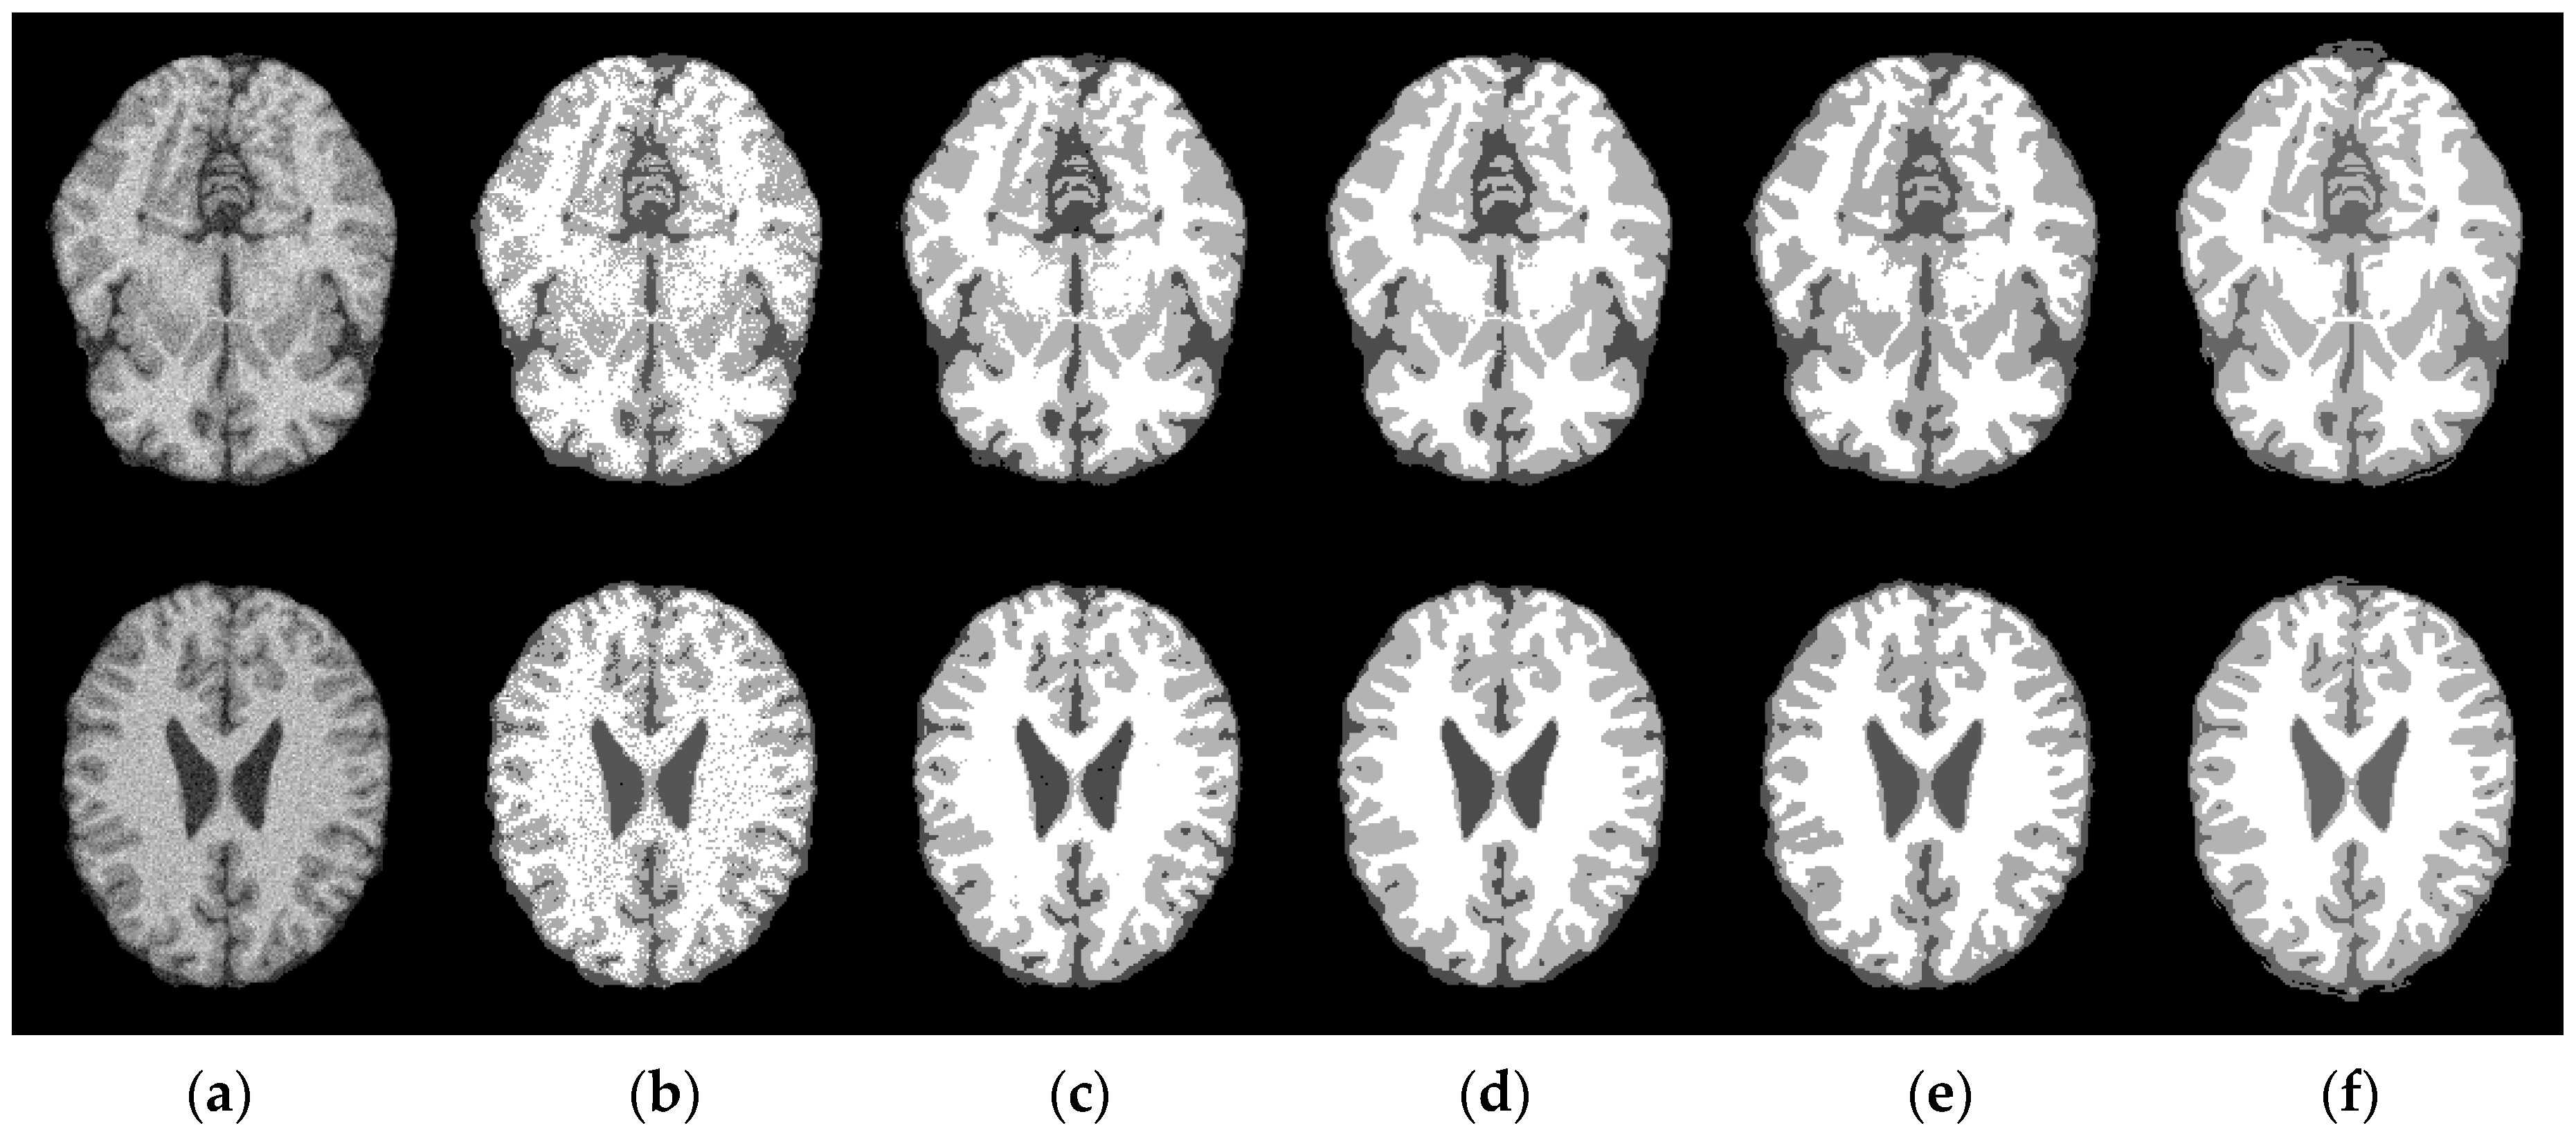

4.1. Robustness to Noise